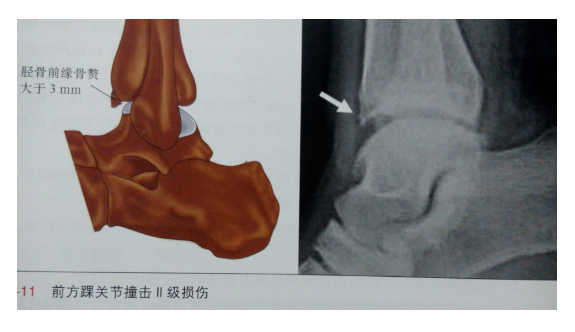

定义:胫骨远端前方或距骨颈异常增生的骨赘突入胫距关节内,在踝关节背屈时产生撞击,造成活动受限和疼痛。多见于运动员及舞蹈演员,侧位X线片是这类损伤最为常用的影像学检查方法。

分级

根据X线片对前方踝关节撞击症进行分级

Ⅰ级:胫骨远端前方出现骨赘(≤3mm)

Ⅱ级:胫骨远端前方出现骨赘(≥ 3mm)

Ⅲ级:胫骨远端前方骨赘合并距骨颈部骨赘

Ⅳ级:胫骨远端前方骨赘与距骨颈部骨赘互相接触